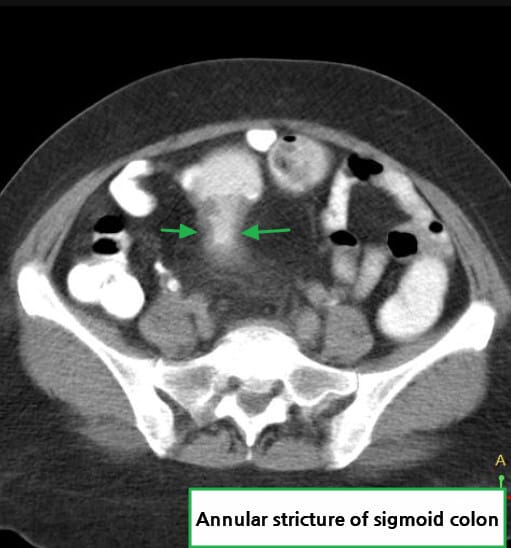

🔵 Annular constricting mass

암이 장을 원형으로 둘러싸며 협착을 유발하는 고전적 폐색 패턴입니다.

Abdrabou A, Carcinoma of sigmoid colon. Case study, Radiopaedia.org (Accessed on 15 Jul 2025) https://doi.org/10.53347/rID-23071